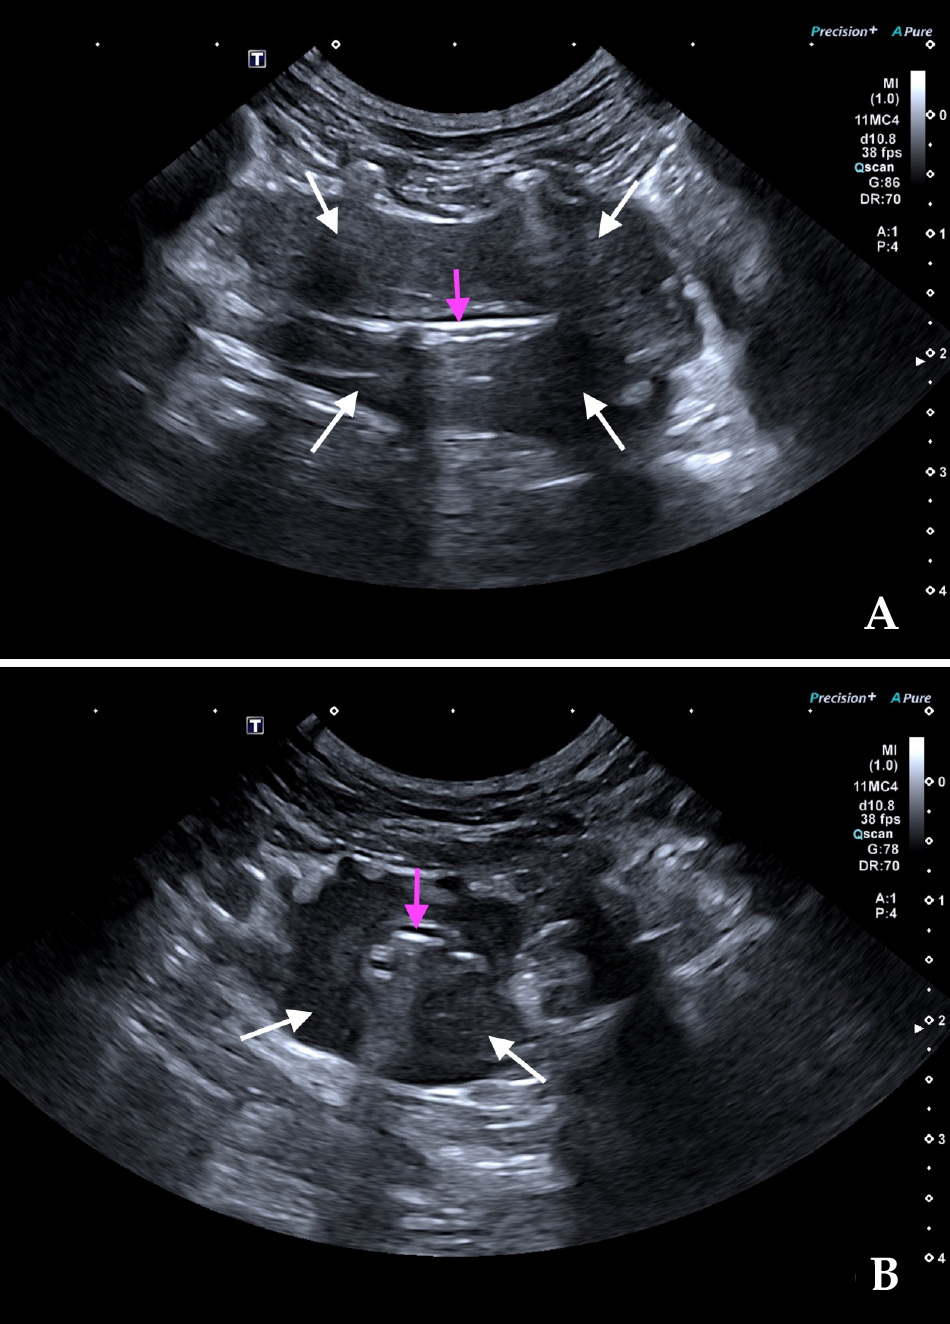

Para llegar al diagnóstico definitivo en este caso se realizó una ecografía torácica y una punción ecoguiada con aguja fina de la lesión. La ecografía mostró una masa concéntrica, hipoecoica y homogénea, de bordes ligeramente irregulares y bien definidos, rodeando la luz traqueal (Fig. 3), y que medía aproximadamente 40 mm de longitud y 18 mm de anchura, con grosores asimétricos desde 3 a 12 mm. Las muestras citológicas presentaban una población linfoide no muy abundante, constituida por linfocitos activados y linfoblastos, lo que confirmaba el diagnóstico diferencial más probable. Además, se realizó una ecografía abdominal que fue compatible con la normalidad.

Imágenes ecográficas en cortes longitudinal (A) y transversal (B) de la masa traqueal obtenidas con abordaje intercostal. Se observa una lesión tipo masa concéntrica, de bordes ligeramente irregulares y bien definidos, hipoecoica y homogénea (flechas blancas) rodeando la luz traqueal (flechas rosas).